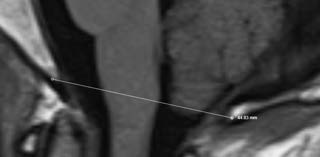

This scan was taken approximately six months after Diane’s treatment. The cerebral tonsil is now above the radiographic line that comes from the base of the skull, creating less compression on the brain stem.